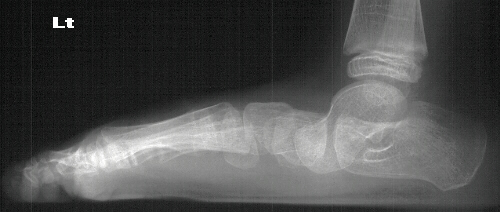

Radiographs reveal the following deformities:

- hindfoot valgus with AP talocalcaneal angle of > 35 degrees

- lateral subluxation/dislocation of the navicular from the talar head

- adduction of the metatarsals with the talus- 1st metatarsal angle to

be divergent medially

- increased lateral talocalcaneal angle with talus plantarflexed on calcaneus

RADIOGRAPHIC FEATURES:

- lateral displacement of the navicular on the head of the talus

- metatarsal adduction

- widening of the talocalcaneal angle on AP radiograph- usually greater

than 35 degrees

- increased lateral talocalcaneal angle with planterflexion of the talus